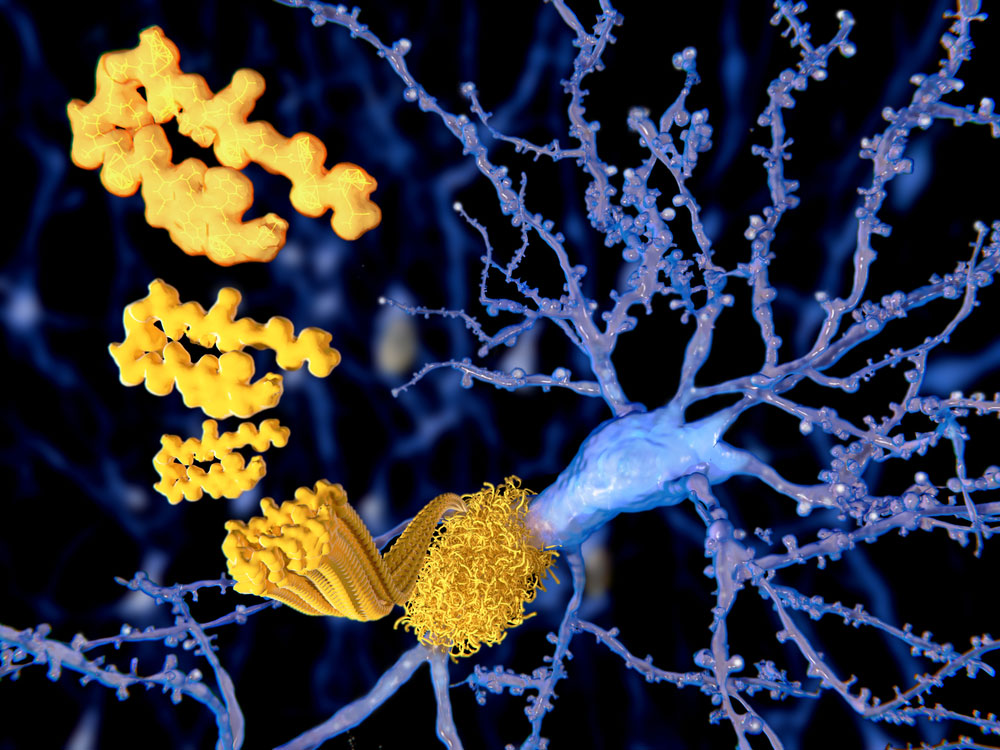

SOD1 protein found to trigger treatable Parkinson’s progression

Scientists at the University of Sydney have discovered a malfunctioning brain protein linked to Parkinson’s - which could lead to new therapies for the debilitating condition in the future.